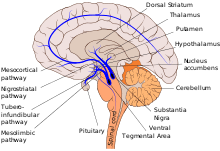

Dopaminergic pathways

Dopaminergic pathways, sometimes called dopaminergic projections, are neural pathways in the brain that transmit the neurotransmitter dopamine from one region of the brain to another.[1][2]

The neurons of the dopaminergic pathways have axons that run the entire length of the pathway. The neurons' somata produce the enzymes that synthesize dopamine, and they are then transmitted via the projecting axons to their synaptic destinations, where most of the dopamine is produced. Dopaminergic nerve cell bodies in such areas as the substantia nigra tend to be pigmented due to the presence of the black pigment melanin.

There are eight dopaminergic pathways. The four major ones are:

The mesolimbic pathway transmits dopamine from the ventral tegmental area (VTA) to the nucleus accumbens. The VTA is located in the midbrain, and the nucleus accumbens is in the ventral striatum. The "meso" prefix in the word "mesolimbic" refers to the midbrain, or "middle brain", since "meso" means "middle" in Greek. |

The mesocortical pathway transmits dopamine from the VTA to the prefrontal cortex. The "meso" prefix in "mesocortical" refers to the VTA, which is located in the midbrain, and "cortical" refers to the cortex. | |||

The nigrostriatal pathway transmits dopamine from the substantia nigra pars compacta (SNc) to the caudate nucleus and putamen. The substantia nigra is located in the midbrain, while both the caudate nucleus and putamen is located in the dorsal striatum. |

| | The tuberoinfundibular pathway transmits dopamine from the hypothalamus (arcuate nucleus aka "infundibular nucleus") to the pituitary gland. This pathway influences the secretion of certain hormones, including prolactin. "Infundibular" in the word "tuberoinfundibular" refers to the cup or infundibulum, out of which the pituitary gland develops. | |||

The mesocortical and mesolimbic pathways are sometimes referred to simultaneously as the mesocorticolimbic projection, system, or pathway.[2][5]